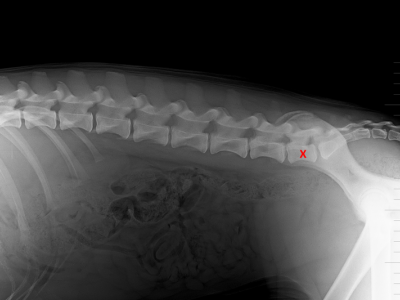

Lumbosakrální přechodový obratel